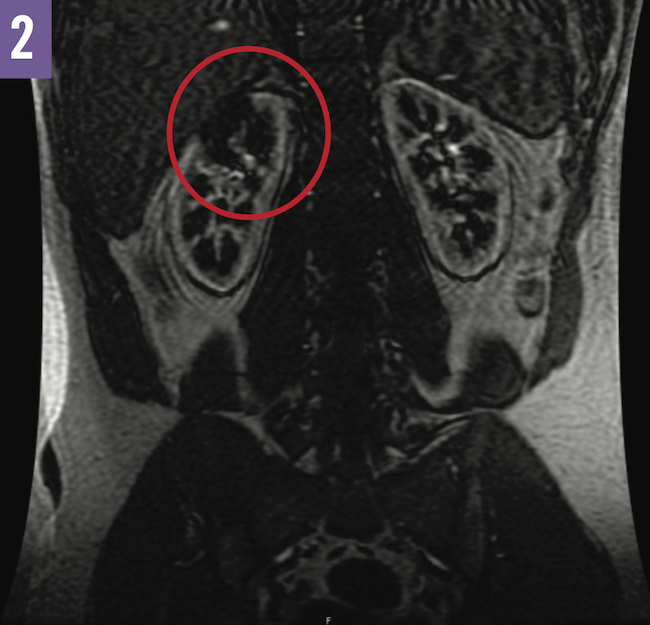

A number of imaging studies were done during his hospital stay. Computed tomography scans of the abdomen and pelvis were suggestive of a renal infarct as opposed to pyelonephritis (Figure 1). Transthoracic and transesophageal echocardiography revealed no apparent thrombi. Magnetic resonance angiography of the abdomen showed evidence of renal upper pole avascularization without abnormalities of the renal arteries (Figure 2).